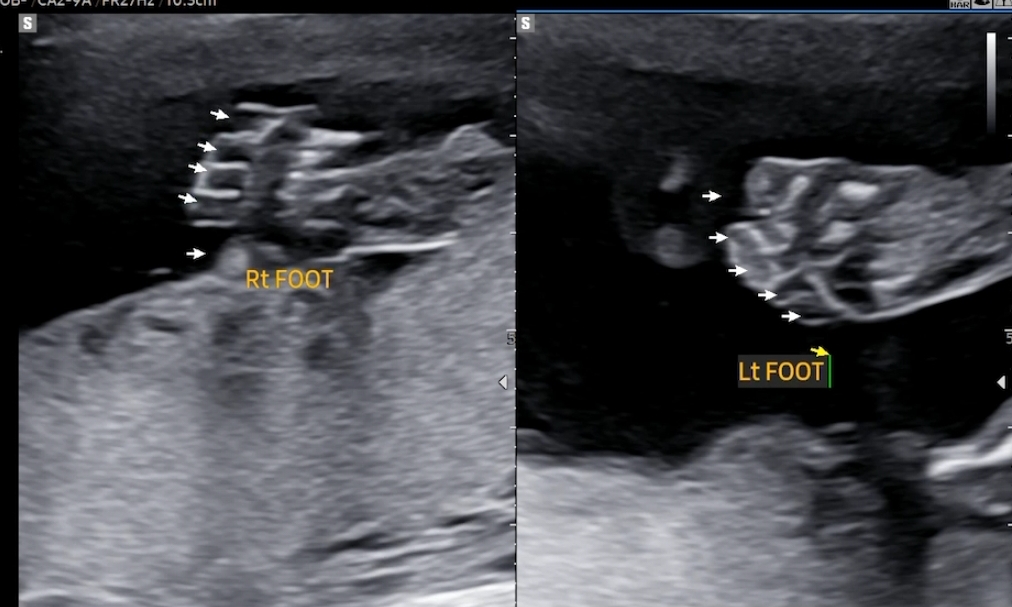

다른분들 정밀초음파에서 늘 보았던 손가락 발가락 세는 과정도 했어요. 5개씩 잘 있었구요.